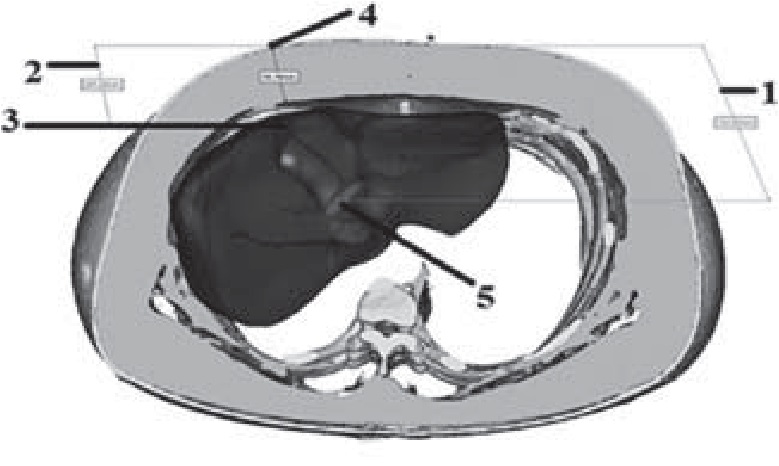

Для определения расстояния от кожи до шейки желчного пузыря в режиме многоплоскостных реконструкций визуализировали общий желчный проток и место его слияния с пузырным протоком и производили маркировку (точка 5). Через эту точку проводили две прямые – одну параллельно сагиттальной плоскости тела, вторую – перпендикулярно. В месте пересечения второй прямой и кожи производили маркировку (точка 6). С помощью измерительных функций в компьютерной программе определяли расстояние (в мм) между точками 5 и 6. Аналогичным способом устанавливали дистанцию от кожи до дна желчного пузыря и расстояние от кожи до задней стенки влагалища прямой мышцы живота (толщину передней брюшной стенки). В сложных случаях использовали компьютерную программу «Mimics» для построения 3D-модели (рис. 5) брюшной полости пациента и выполняли виртуальный оперативный доступ с расчетом его критериев.

Рис. 5. Измерение глубины раны и толщины подкожной клетчатки на аксиальном срезе 3D-модели: 1 – расстояние от шейки желчного пузыря до кожи; 2 –расстояние от кожи до дна желчного пузыря (толщина ПБС); 3 – дно желчного пузыря; 4 – точка 6; 5 – шейка желчного пузыря (точка 6)